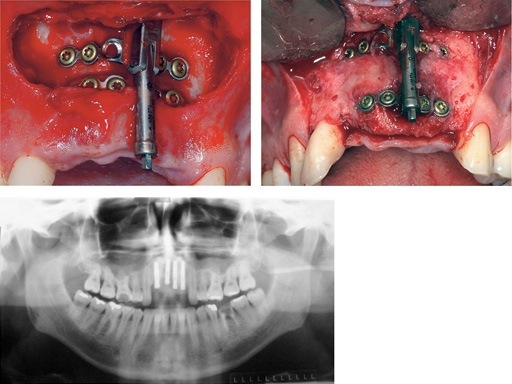

Maxillary distraction in a 34-year-old male after periodontal disease.

Mandibular distraction in a 20-year-old male after trauma. The bone biopsy shows a darker shading where the bone is newly formed.